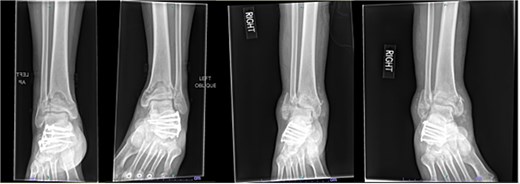

A 38-year-old male with a BMI of 27.5 kg/m2 and a history of alcohol use disorder, paranoid schizophrenia, smoking, and prior bilateral calcaneal fractures treated with ORIF 4 years earlier sustained bilateral pilon fractures after jumping from a third-story window (Fig. 3). He presented to the hospital 5 days after injury.

AP and oblique radiographs of patient 2 obtained after a fall, demonstrating bilateral pilon fractures and retained hardware from prior bilateral calcaneal ORIF.

Initial surgery occurred 3 days after presenting to the hospital and involved definitive ORIF of the left leg using a distal tibial locking plate and a distal fibular locking plate. At the time of the initial surgery, there were significant fracture blisters that prevented definitive fixation of the right leg; thus, an external fixator was applied to the right leg. One week later, ORIF of the right leg was performed with distal tibial and fibular locking plates. The patient was made NWB bilaterally and required a wheelchair for mobility during the first 12 weeks. Although he was instructed to use crutches once partial weightbearing (PWB) was permitted, he demonstrated poor adherence to these restrictions.